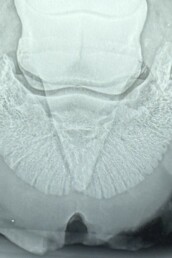

- Röntgenuntersuchung, um Veränderungen im Hufinneren darzustellen

- Ausschneiden des Hufes, wobei schwärzliches Sekret austrat – Hinweis auf eine Infektion

Damit war die Diagnose Hornsäule mit bakterieller Infektion gesichert.